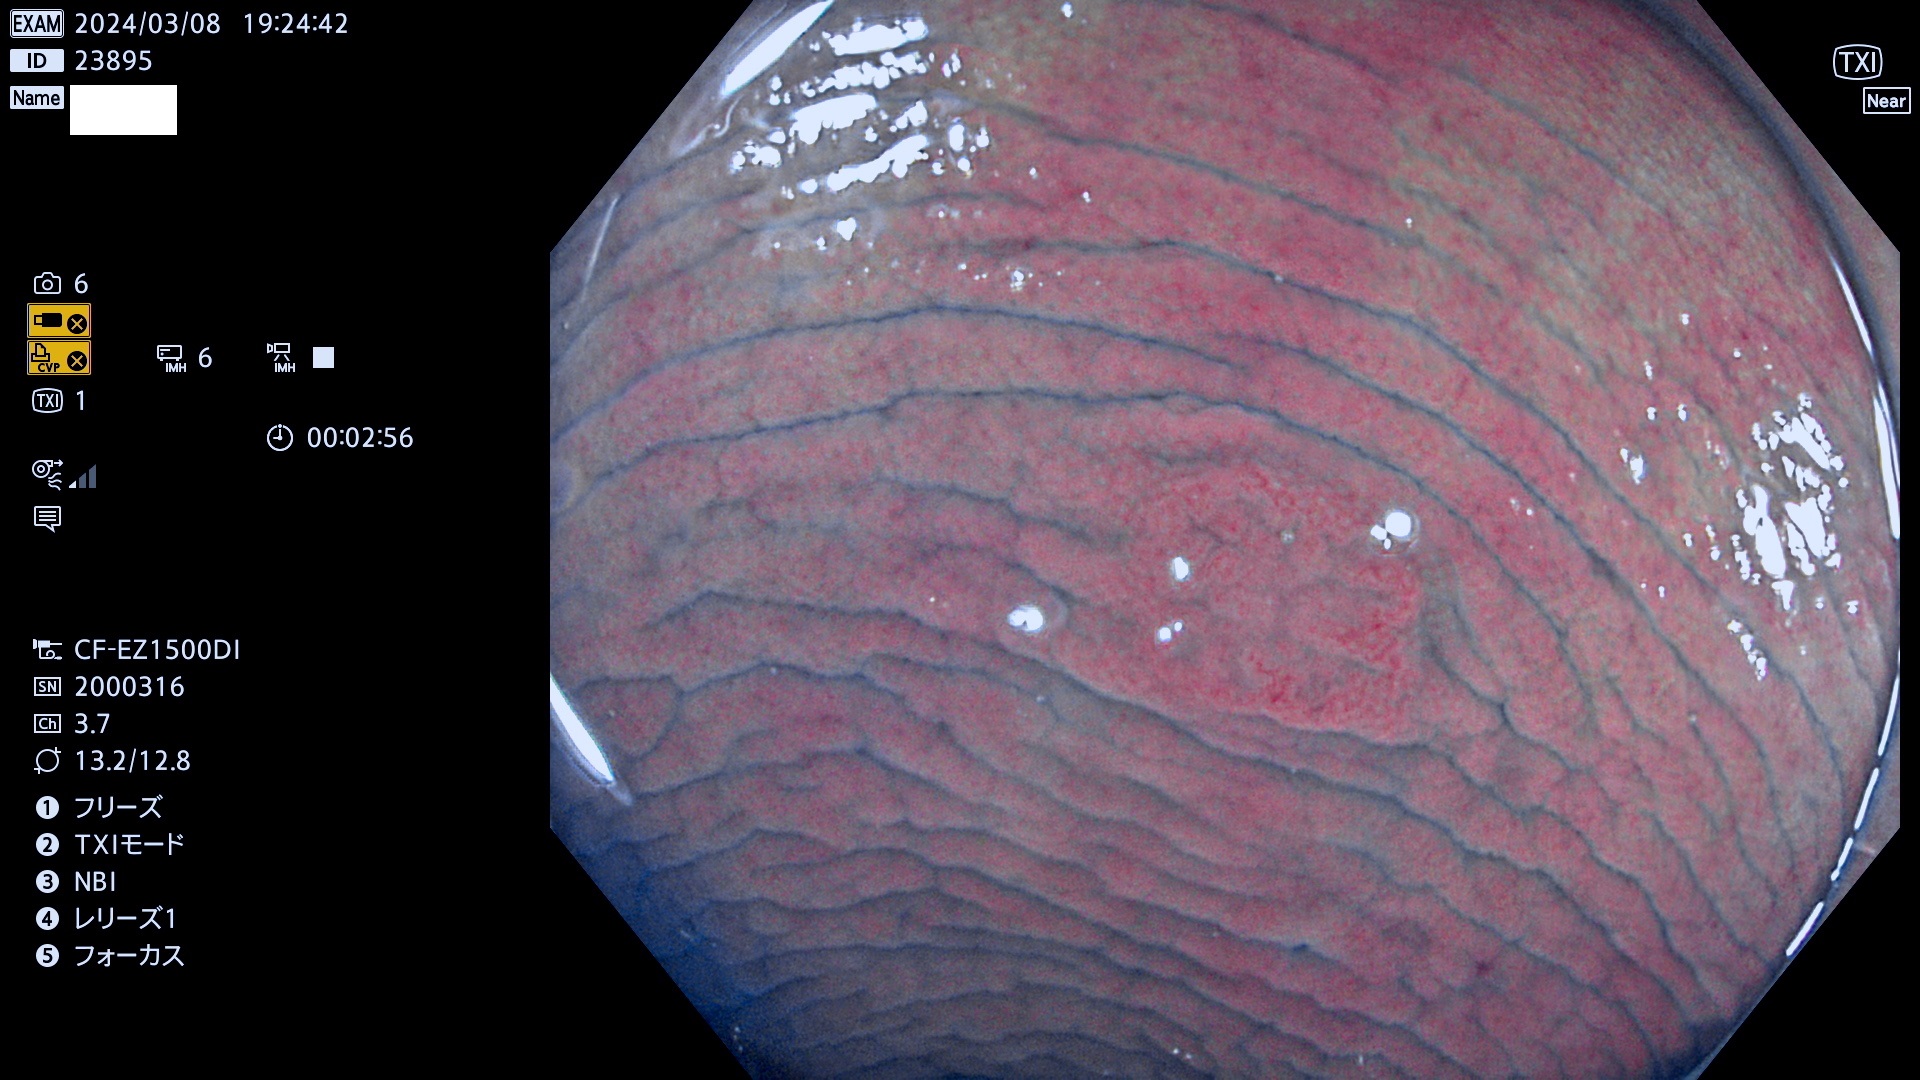

今週のUb、Uc型腺腫

表面型腺腫(Flat Adenoma)の中で、完全に平坦な物をUb、陥凹している物をUcと呼びます。平坦隆起型(Ua)よりも、発見が難しく危険な病変です。

毎週の検査(木・金・土・日)に発見されたUb、Uc型・腺腫を、その週の日曜の夜にUPし1週間、提示します。

抽出の対象期間 2024年3月7日(木)〜3月10(日)の4日間(40件の検査)6件 (6/40=13%)